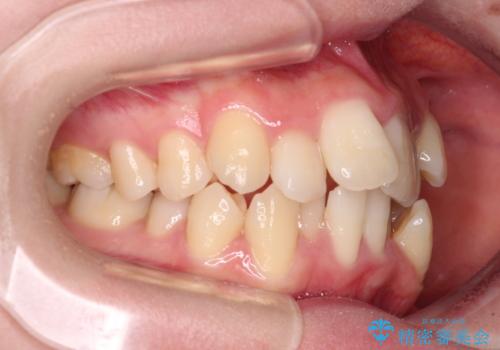

- 上下前歯の八重歯やデコボコと、唇の閉じにくさを気にして来院された患者様です。

口元の突出感を改善するため、上下左右の第一小臼歯4本を抜歯し、ワイヤー装置にて矯正治療を行うこととしました。